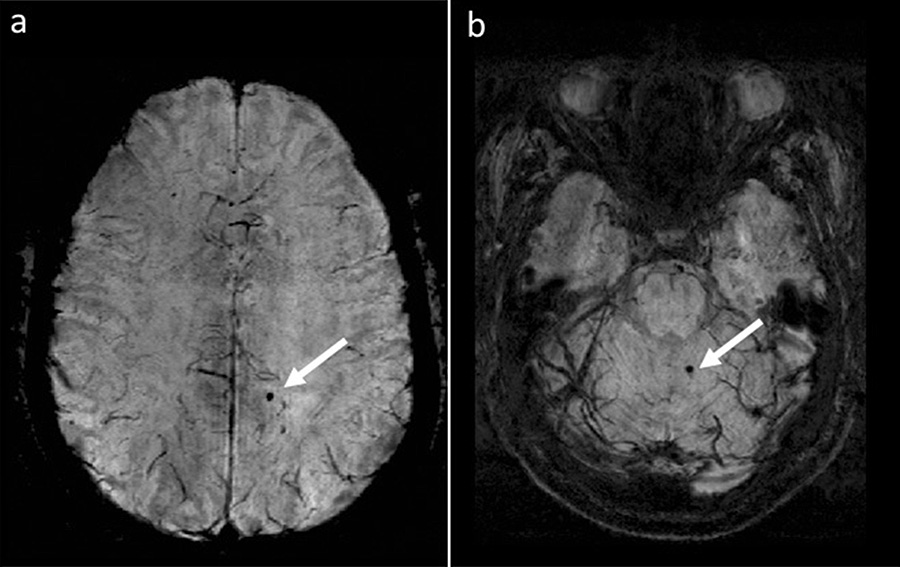

Researchers in the Jacobs School of Medicine and Biomedical Sciences at UB are continuing to study cerebral microbleeds, identified in the images above, as indicators of disease progression in multiple sclerosis.

All study participants underwent a type of magnetic resonance imaging called susceptibility-weighted imaging that is specifically targeted to better image blood products.